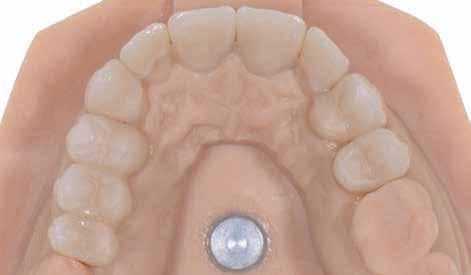

A szakirodalomban fellelhető eredmények alapján kerámia héjak ragasztására a kontaminációtól mentes, frissen vágott zománc felszín a legalkalmasabb. A hosszú távú sikeresség elérésének további feltétele a fogak konzervatív módon történő preparálása, továbbá a ragasztás kofferdám felhelyezésével biztosított, abszolút izolálásban történő kivitelezése. Úgy véljük, hogy a fenti faktorok biztosították a cikkben bemutatásra kerülő esetek – 5 évvel az átadás után megfigyelhető – sikerességét. A kofferdám izolálás alkalmazása számos előnyt biztosít a gyakorló fogorvos számára. Megakadályozza a munkaterület nyállal, vérrel, vagy szulkusz-váladékkal történő kontaminációját, és javítja a kezelendő területre való rálátásunkat. A fogak kerámia héjak ragasztása előtt történő izolálása azonban gyakran kihívást jelenthet a kevesebb klinikai tapasztalattal rendelkező fogorvosok számára. Jelen esetbemutatásban ismertetjük a kofferdám felhelyezésének lépéseit és néhány olyan gyakorlati tanácsot, amelyek jelentősen megkönnyíthetik a munkánkat, azokban az esetekben, amikor a második kisőrlőfogak közti területet kívánjuk kofferdám segítségével izolálni. A kofferdám kapcsok segítségével került rögzítésre, majd fogakat körülvevő széleit óvatosan az ínybarázdába forgattuk. A kerámia héjak számára előkészített fogakra ragasztás előtt egyenként kapcsokat helyeztünk annak érdekében, hogy a kerámia héjak rögzítése ideális körülmények között történhessen. A lépések részletes ismertetése segítséget jelenthet – a kevesebb klinikai tapasztalattal rendelkező fogorvosok számára – az abszolút izolálás megvalósításához szükséges lágyrészmenedzsment megértéséhez. Ezek az ismeretek rendkívül hasznosak lehetnek, ha a jövőben a kerámia héjak ragasztását megfelelő módon megvalósított kofferdám izolálás mellett kívánják kivitelezni. A cikkben ismertetett módszerek alkalmazásával az abszolút izolálás megvalósítható, a gumilepedő – vérzés nélkül – ínybarázdába történő beforgatására, és a ragasztáshoz szükséges idő csökkentésére.

Az előzetes állapotfelmérést és a kezelés megtervezését követően a fogakat minimál invazív módon preparáltuk (1. a-b ábrák), majd az előkészített fogak ínybarázdáiba fonalbehelyező eszköz segítségével (113 Serrated Gingival Cord Packer, Hu-Friedy, Chicago, Illinois) teflonszalagot helyeztünk (Loctite Thread Seal Tape, Henkel Loctite Corp., Egyesült Államok), (1. c ábra). A hagyományos retrakciós fonalak helyett, a rugalmasságuk miatt előnyösebbnek tartjuk a teflonszalagok használatát. A kofferdámot (Dental Dam, Nic Tone, Bukarest, Románia) az előkészített fogakon kívül, az azoktól disztálisan elhelyezkedő egy-egy fognak megfelelően is perforáltuk.

Mivel a felső fogív első kisőrlőfogtól ellenoldali első kisőrlőfogig terjedő részét terveztük kerámia héjak segítségével ellátni (14-24), ezért az izolálást ugyanezen fogív második kisőrlőfogtól második kisőrlőfogig terjedő részére (15-25) helyeztük fel (2. a ábra). A kofferdám rögzítését a második kisőrlőfogakra helyezett kapcsok segítségével (Rubber Dam Clamps #2, Hu-Friedy, Chicago, Illinois, Egyesült Államok) biztosítottuk (2. b ábra). Ezt követően a gumilepedő fogakat körülvevő szélét kézi fonalbehelyező eszközzel és finom levegőáramlattal az ínybarázdákba forgattuk. A folyamat a következőképpen zajlott: a kézi eszközzel a kofferdámot a fognyaknak megfelelően finoman a szulkusz irányába fordítjuk, majd az eszköz végét a fognyaknak megfelelően vezetjük, miközben a lepedőt a puszterből jövő levegő segítsé-